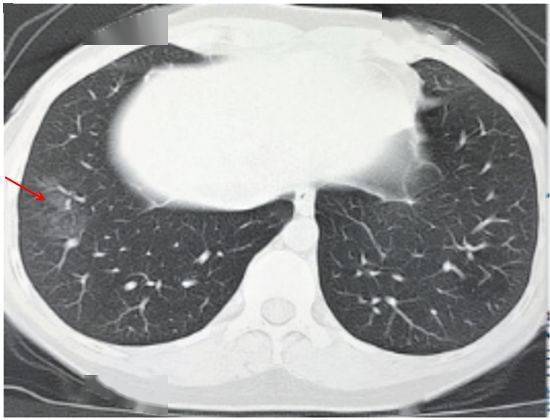

(一)病灶分布

病灶以 肺外围背侧为主,以两肺下叶为著,与胸膜常紧贴,提示新冠肺炎病变多首先侵犯皮层肺组织的细支气管及肺泡上皮, 病灶分布逐步从外周向中央扩展(图 2-1)

图2-1 早期病灶多数分布贴近胸膜( 共4张 )